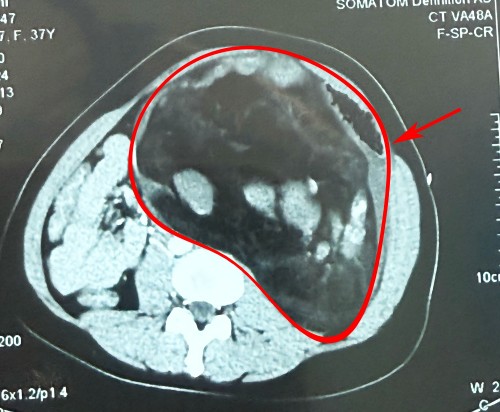

CT显示:左肾巨大错构瘤破裂,大小约为30×30×7cm

泌尿外科一病区李远伟主任医师、刘哲主任医师团队为李女士施行急诊全麻下左肾巨大错构瘤切除术+保留肾单位肾部分切除术+肾周围粘连松解术。术中发现,左侧巨大肿瘤占据患者的整个腹腔,紧贴周围脏器,同时将周围血管组织挤压变形,粘连严重,且肿瘤已破裂出血。既要保证周围脏器及血管不受损还要保证患者的安全,对手术医生来说难度极高。同时由于患者出血过多,术中血压一度降到极低水平,李远伟主任医师、刘哲主任医师临危不乱,手术团队密切配合,凭借高超精湛的专业技术,小心翼翼地进行剥离、止血,避免损伤周围脏器及重要血管,最后快速将肿瘤切除。手术历时5小时,不仅顺利将大小为30×30×7cm,重达7.5kg的“怪胎”完整切除,而且最大程度保留了左肾正常组织及肾功能,成功为李女士“卸货”。